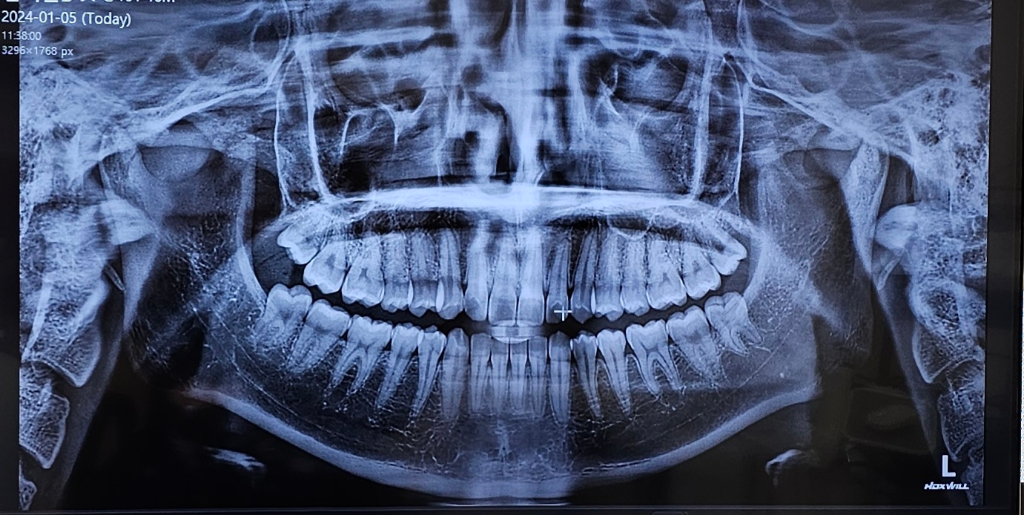

사랑니가 완전히 나오지 못한 것으로 보입니다. 이럴 경우 그냥두면 지속적으로 염증이 반복되니 뽑는 것을 추천합니다. 사랑니 중에서 발치 난이도는 중간정도로 보입니다.

사진 으로 봤을 경우에는 사랑이는 올바로 나고 있는 것으로 보입니다.

완전히 맹출된 것은 아니기 때문에 맹출되는 과정에서 잇몸이 붓거나 할 수 있으며 사랑니는 맨 뒤에 나는 지하로 관리를 하기가 쉽지 않습니다. 따라서 너무 자주 붓거나 불편감이 있다면 사랑니를 발치해 주는 것이 더 좋을 수도 있습니다

1. 양쪽 위아래로 사랑니는 모두 나왔고 비교적 바르게 나온 편입니다.

2. 오른쪽 아래 사랑니의 경우 다만 사이 충치가 의심됩니다.

3. 매복사랑니가 아니기 때문에 생각하시는 것처럼 고난이도 발치 수술은 아닐 것으로 예상됩니다만 실제 상황은 다를 가능성도 있습니다.

저정도 사랑니는 4개다 똑바로 맹출되신거 같습니다. 가장 끝에 잇는 4개의 치아가 사랑니 입니다.